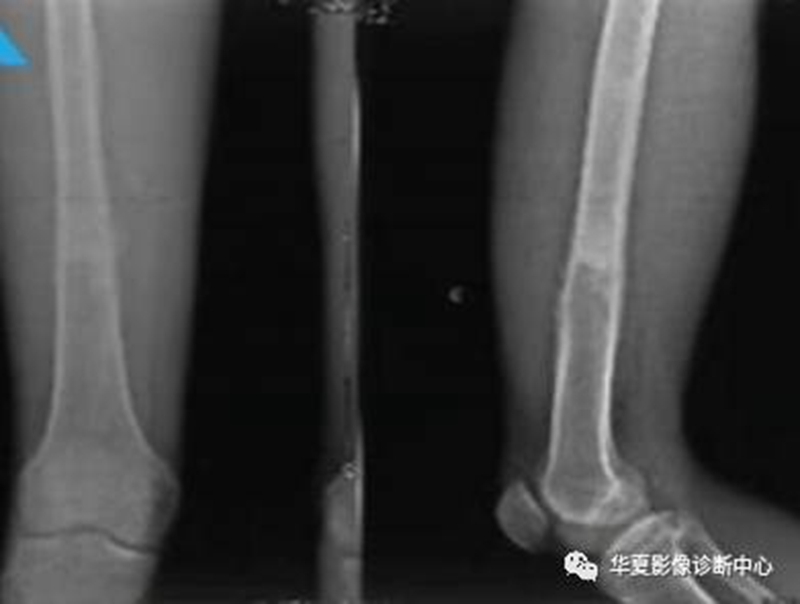

骨样骨瘤良性骨膜反应,骨肉瘤恶性骨膜反应